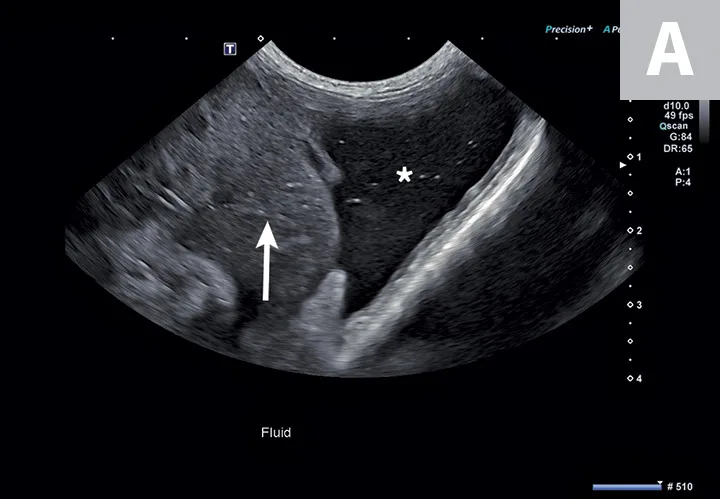

2. Identification of Peritoneal, Pleural, & Pericardial Effusion

Patients with cavitary effusion can have a range of clinical signs, many of which are nonspecific because cavitary effusions are sequelae to a variety of disease processes.5 Ultrasonography is useful in the identification and sampling of effusion fluid in cats and dogs and is more sensitive in the detection of smaller volumes than radiography.6 Primary body cavities to evaluate for effusion include the abdomen (peritoneal space), thorax (pleural space), and pericardial space (Figure 2).5

FIGURE 2

Abdominal effusion (A; asterisk) adjacent to a normal spleen (arrow). Abdominal carcinomatosis with secondary neoplastic effusion was diagnosed. Left parasternal short-axis view of a heart with pericardial (B; asterisks) and pleural effusion (arrow).

The abdomen is most commonly evaluated with the patient in dorsal or lateral recumbency, but scanning the dependent portion with the patient in lateral recumbency can be helpful if only a small amount of effusion is present (see Suggested Reading).6,7 Evaluation for pleural effusion is performed with the patient standing or in ventral recumbency and should begin at the eighth to ninth intercostal space at the level of the costochondral junction. This space is also recommended when thoracocentesis is used in these patients.8 Evaluation for pericardial effusion in the right third to fifth intercostal space at the level of the costochondral junction provides the best acoustic window to the heart.5

Cavitary effusion is normally anechoic on ultrasound but can differ based on fluid type.6 Echogenicity and cytologic classification of effusion is based on cellular and protein content, increasing in echogenicity from pure transudate (anechoic) to modified transudate (variably echoic) and exudate (hyperechoic)6,9; however, the echogenicity of cavitary fluid can vary; thus, fluid analysis is required to confirm the exact nature of the fluid.